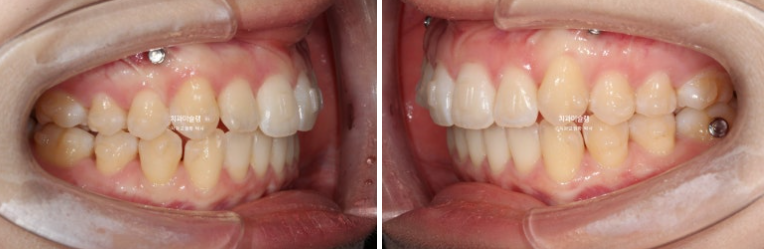

고무줄을 열심히 껴준 탓에 좌측 교홥관계는 좀 더 1급에 가까워졌습니다.

25.01~25.11

우측은 완벽한 1급을 달성했습니다